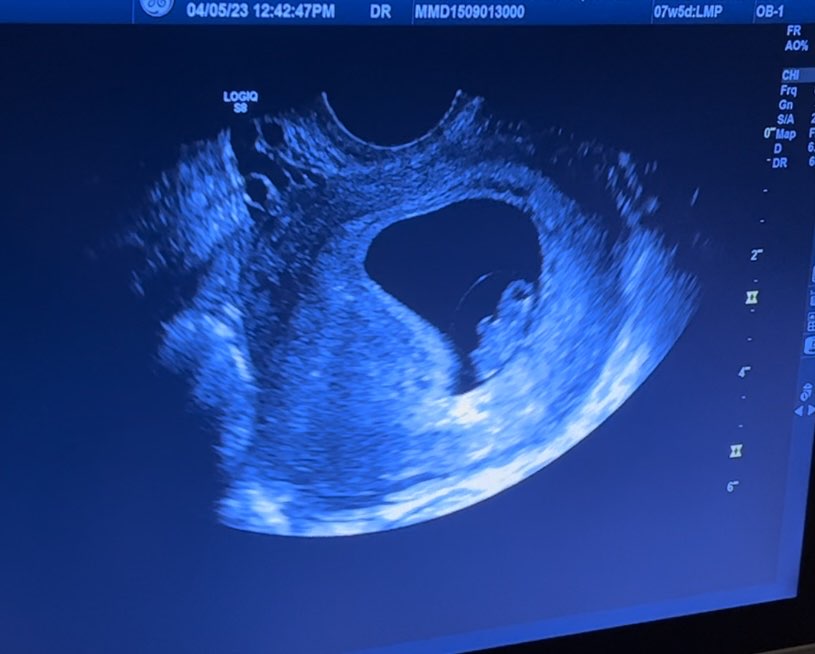

Jestem dziewczyny! Maleństwo żyje i ma się dobrze, ma aktualnie 1,45cm. 🥰 Serduszko bije już prawidłowo. Krwiak się jeszcze do końca nie wchłonął ale już jest mniejszy. Mi za to doszły leki na nadciśnienie bo do tej pory nie brałam (od kilku lat) a dziś moje ciśnienie wynosiło 160/100 i tętno 120 co jest u mnie dobrym wynikiem ale niekoniecznie bezpiecznym w ciąży... Także póki co dalej jakoś ciągniemy. 😊